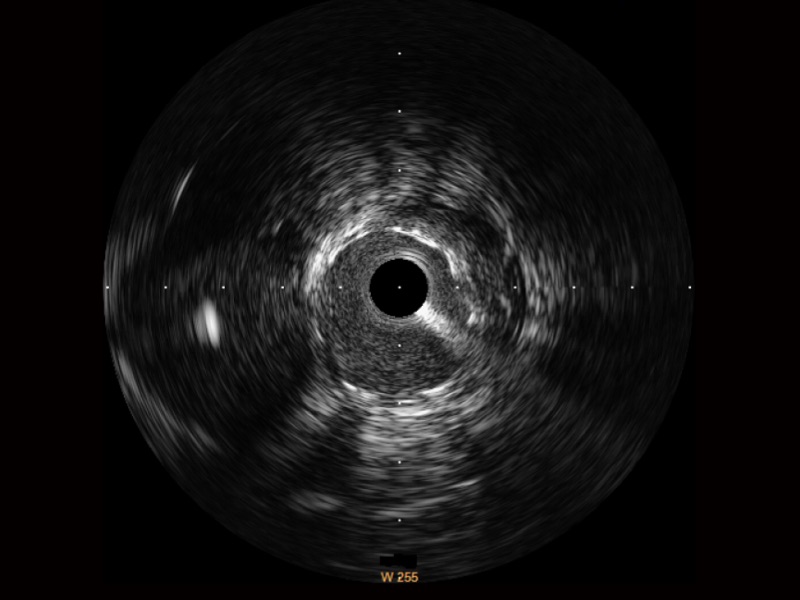

• 传统IVUS图像

对比传统IVUS导管成像,16877太阳集团宽频IVUS图像的近场支架梁显影更细腻,远场中膜外血管仍清晰可辨,兼顾远中近,兼顾分辨力与穿透深度